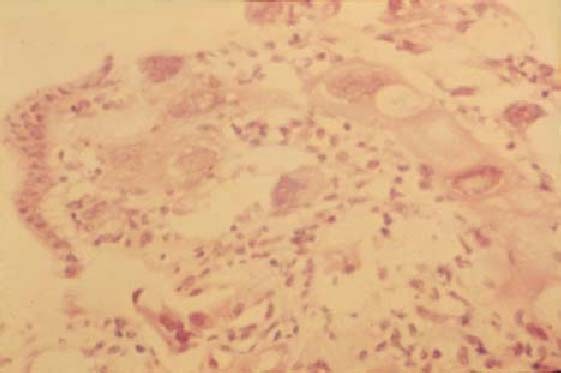

The first case of percutaneous transhepatic bile duct biopsy in the world. This is a case of recurrent gastric cancer combined with obstructive jaundice. The bile cytology showed that it was Class 1 but the result of biopsy exactly revealed the existence of cancer cells in tissues under the epithelium of the bile duct

Fig. 7

figure 7

Biopsied specimen through percutaneous transhepatic bile duct biopsy. The membrane of the bile duct was normal; however, cancer cells were found in tissues under the membrane of the bile duct